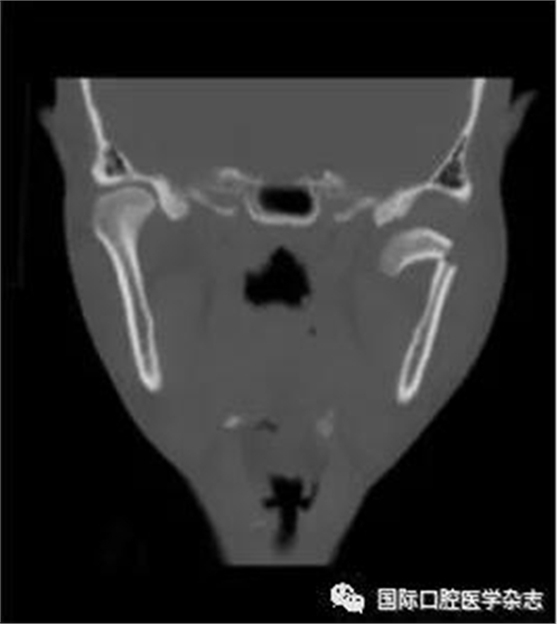

(4)關(guān)節(jié)強(qiáng)直(圖3):指因器質(zhì)性病變導(dǎo)致長(zhǎng)期開口困難或完全不能開口??煞譃殛P(guān)節(jié)內(nèi)強(qiáng)直和關(guān)節(jié)外強(qiáng)直。關(guān)節(jié)內(nèi)強(qiáng)直是由于一側(cè)或兩側(cè)關(guān)節(jié)內(nèi)發(fā)生病變,造成關(guān)節(jié)內(nèi)的纖維性或骨性粘連,也有人稱為真性關(guān)節(jié)強(qiáng)直。關(guān)節(jié)外強(qiáng)直是病變位于關(guān)節(jié)外上下頜間皮膚、黏膜或深層肌肉組織,形成頜間瘢痕攣縮(圖4),也有人稱為假性關(guān)節(jié)強(qiáng)直[7]。5)顳下頜關(guān)節(jié)感染:常由下頜關(guān)節(jié)附近化膿性病灶所致。多見于兒童中耳炎、腮腺炎等。此外還可由全身性傳染性疾病如麻疹、猩紅熱等引起。6)顳下頜關(guān)節(jié)外傷(圖5):外傷是引起開口受限的常見因素之一,最常見于下頜骨髁突骨折引起下頜運(yùn)動(dòng)受限[8]。

圖 4 頜間攣縮